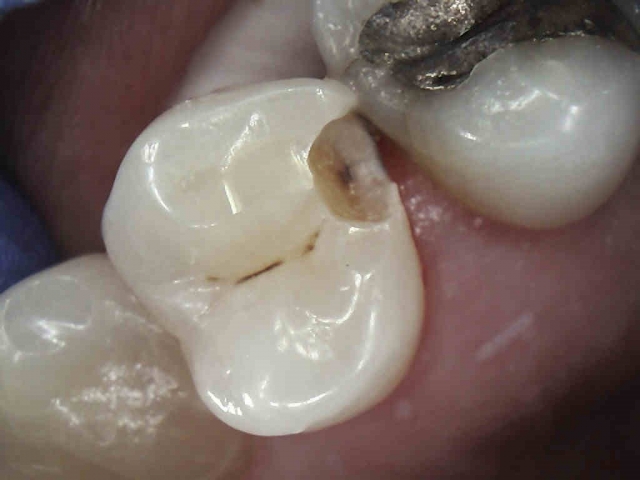

Patient 4: Teeth #12 and #13

On the black-and-white image, the patient has caries on #12, #13, #18, #19 and #20. We will focus on #12 and #13, especially the mesial of #13. The black-and-white image is less suggestive there than on #12. The photo tells a very different story. #13 is more advanced.